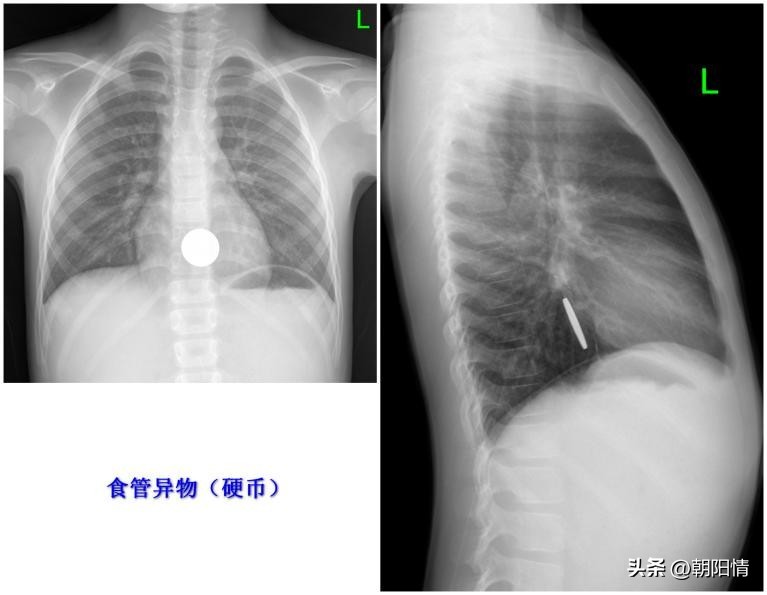

Case1 :胸部正侧位片观察食管硬币

随着多层螺旋CT的发展及其重建技术的应用,多层螺旋CT可以明确消化道异物的诊断,了解异物的大小、形态及异物与周围组织的关系,观察食管、肠管周围是否存在并发症。为临床提供丰富的诊疗信息,具有重要的参考价值。

传统检查有X线平片,包括颈椎正侧、胸部正侧及腹部平片,对于怀疑鱼刺类异物采用钡棉钩挂法。但是X线平片有一定的局限性,对阴性的异物难以明确。钡棉钩挂时对食管产生机械性挤压,有加重食管二次损伤的风险。